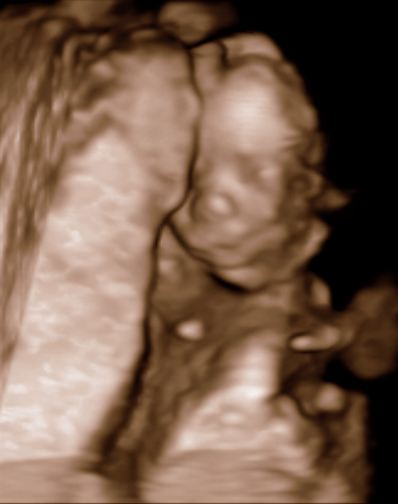

Мои неделькиНу вот и я решилась представить и рассказать, как мы живём вот уж как 22 недельки вместе с малышом :)

Прекрасные фоточки, мой тоже в прошлом году УЗИ начинал с демонстрации *я мальчик!*